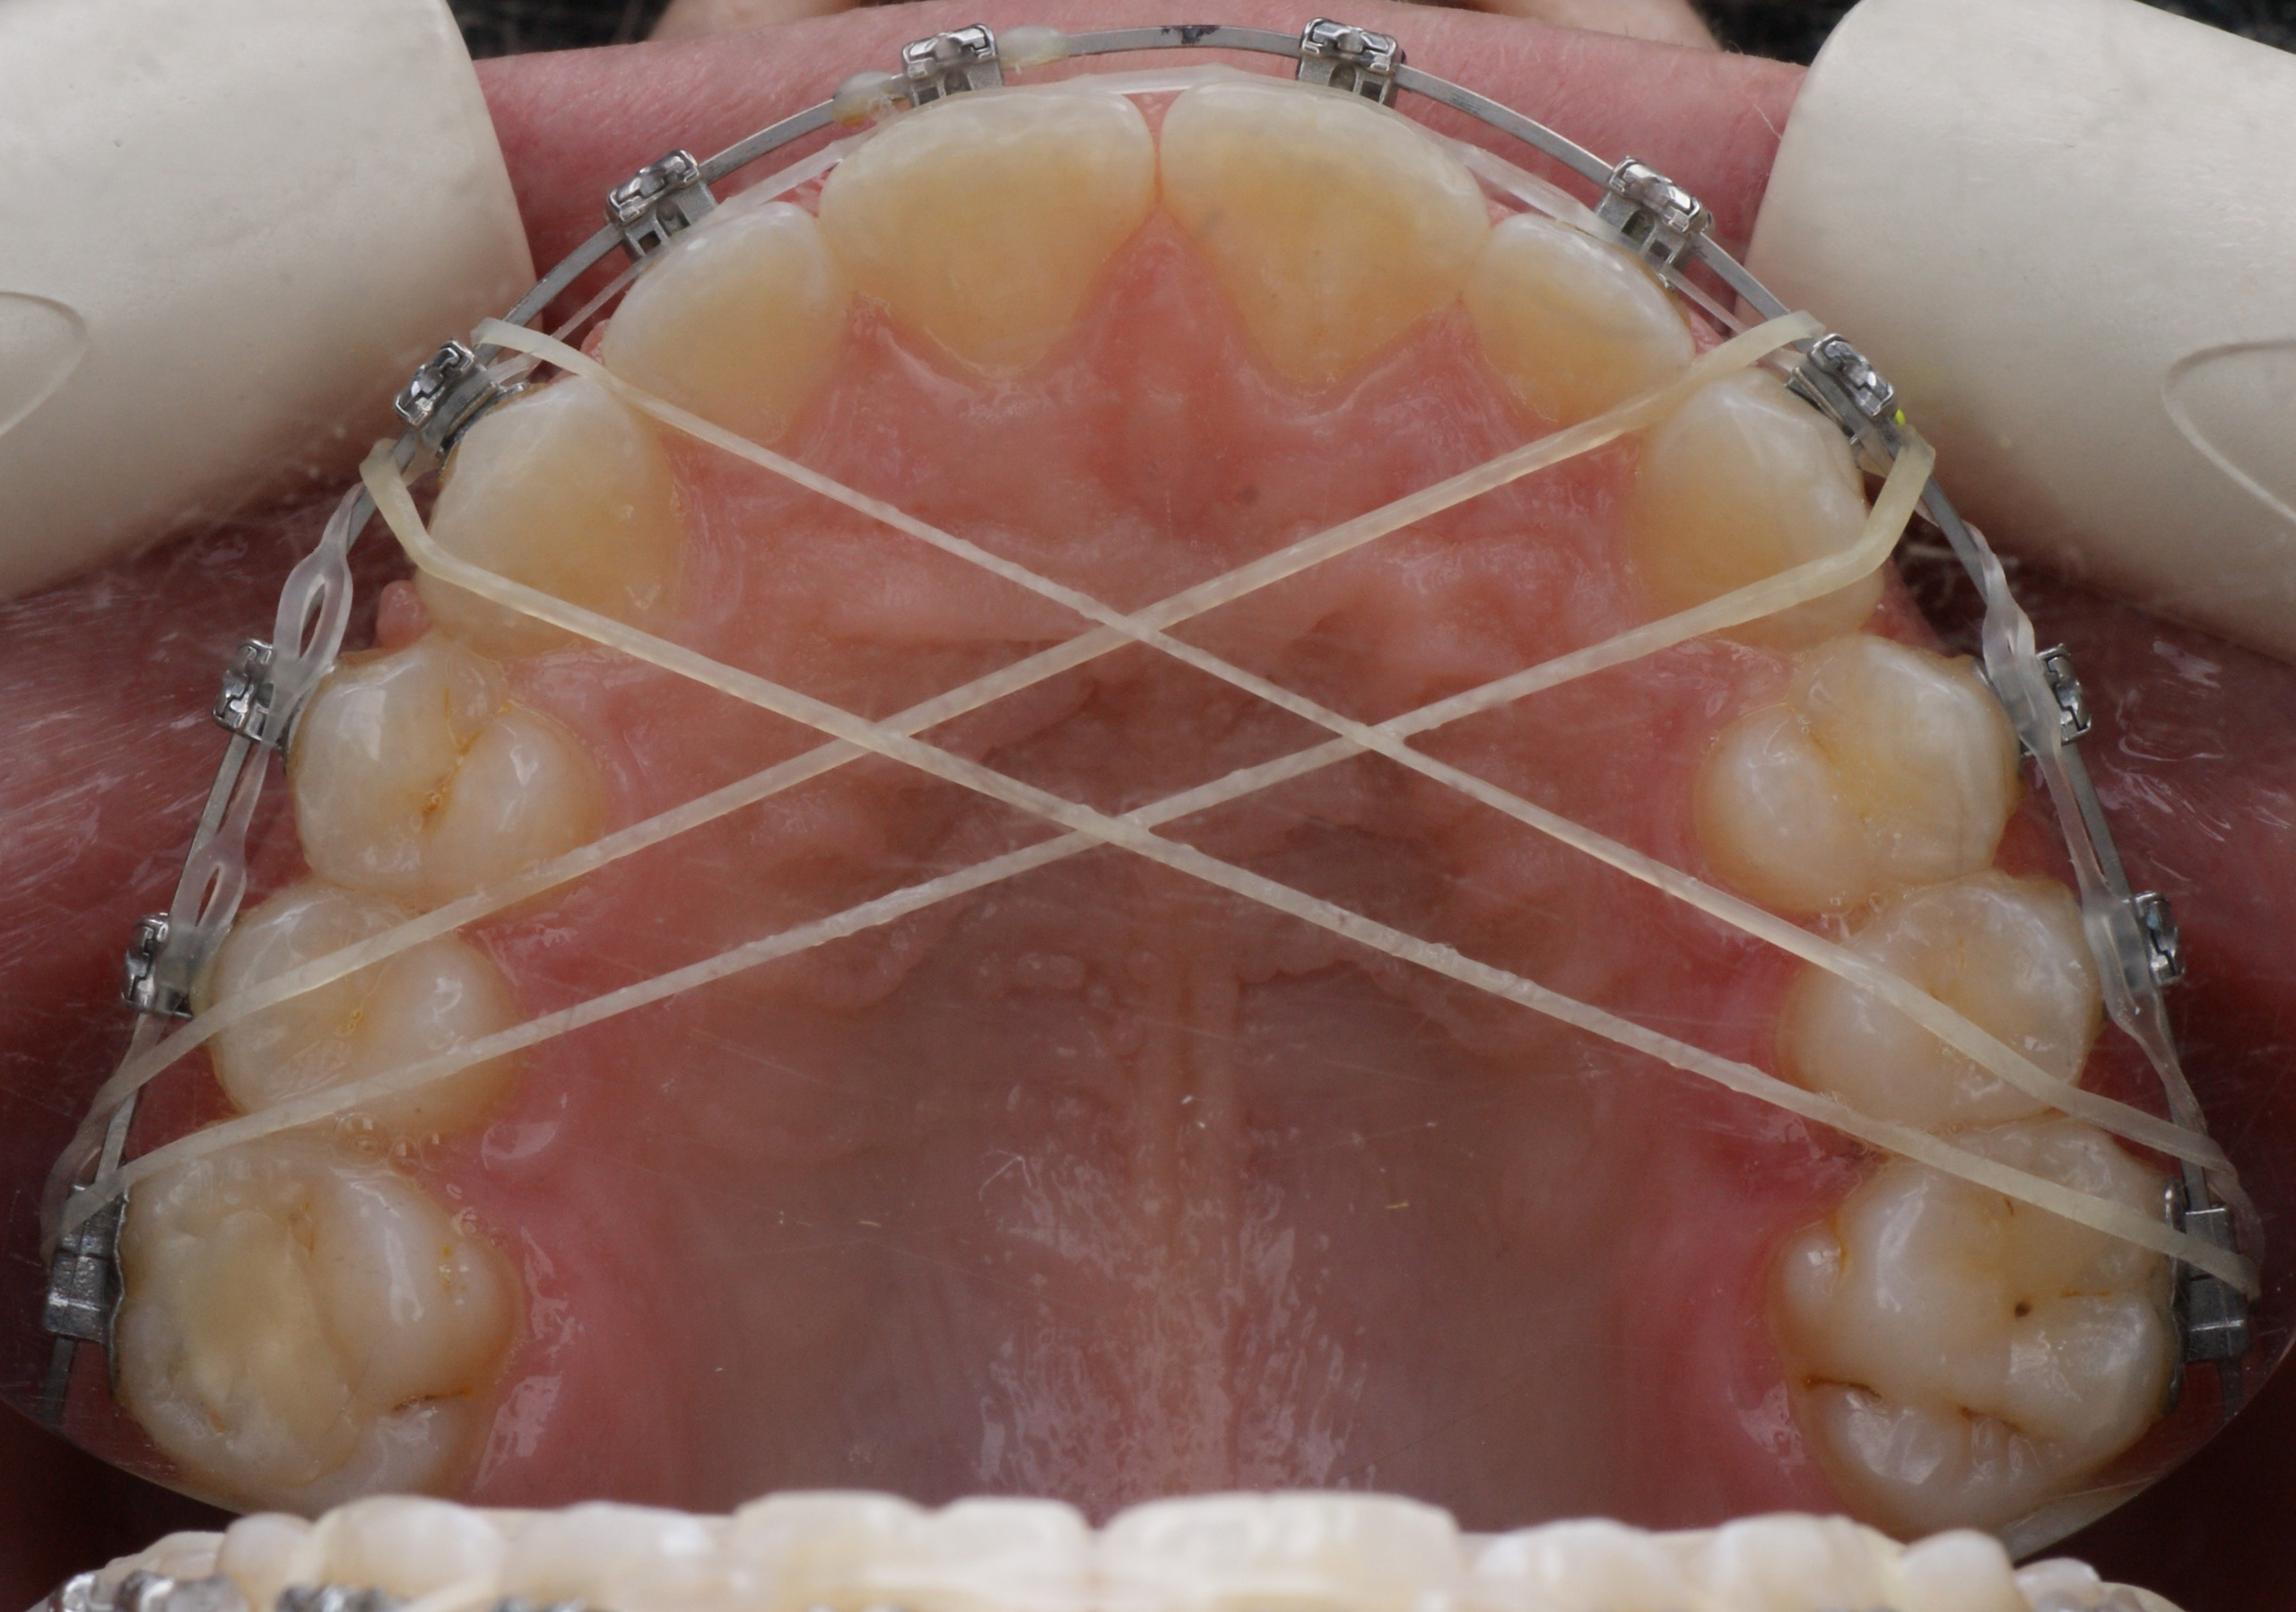

Расширение 🔜 Сужение Эластики (резиновая тяга) через нёбо могут использоваться для сужения зубного ряда.

Сужение 🔜 Расширение Изменение формы верхней челюсти во время лечения.

КАК УСТАНАВЛИВАЕТСЯ АППАРАТ МАРКО РОСА (Marco Rosa)

1️⃣ Установка сепарационных колец (голубые резиночки) в промежутки между опорными зубами для их небольшого раздвижения друг от друга и создания места для колец аппарата. Устанавливаются на 10-20 минут (могут устанавливаться на несколько дней).

2️⃣ Очистка опорных зубов от налёта с помощью специальной пасты и вращающейся щеточки бормашины.

3️⃣ На кольца наносится специальный стоматологический клей. Аппарат фиксируется во рту. Клей отверждается световой лампой. Добавляется клей на лапки молочных клыков.

КОНСТРУКЦИЯ АППАРАТА МАРКО РОСА

1️⃣ ВИНТ ХАЙРЕКС. Создаёт расширяющее усилие.

2️⃣ МЕТАЛЛИЧЕСКИЕ ЛАПКИ. Это дополнительные элементы фиксации, которые упираются в молочные клыки, создают точки приложения силы к зубному ряду.

3️⃣ КОЛЬЦА НА МОЛОЧНЫЕ МОЛЯРЫ. Обеспечивают фиксацию аппарата на опорных зубах с помощью специального стоматологического клея.

4️⃣ ПЛАСТМАССОВЫЙ БАЗИС (пластинка). Объединяет все элементы в единую систему и передаёт расширяющее усилие винта на нёбо.

5️⃣ ДОПОЛНИТЕЛЬНЫЕ ЭЛЕМЕНТЫ (крючки для лицевой маски)

*️⃣ Спанч Боб и Патрик😀

Аппарат Марко Роса (Marco Rosa) - маленький невидимый помощник в больших ортодонтических делах💗